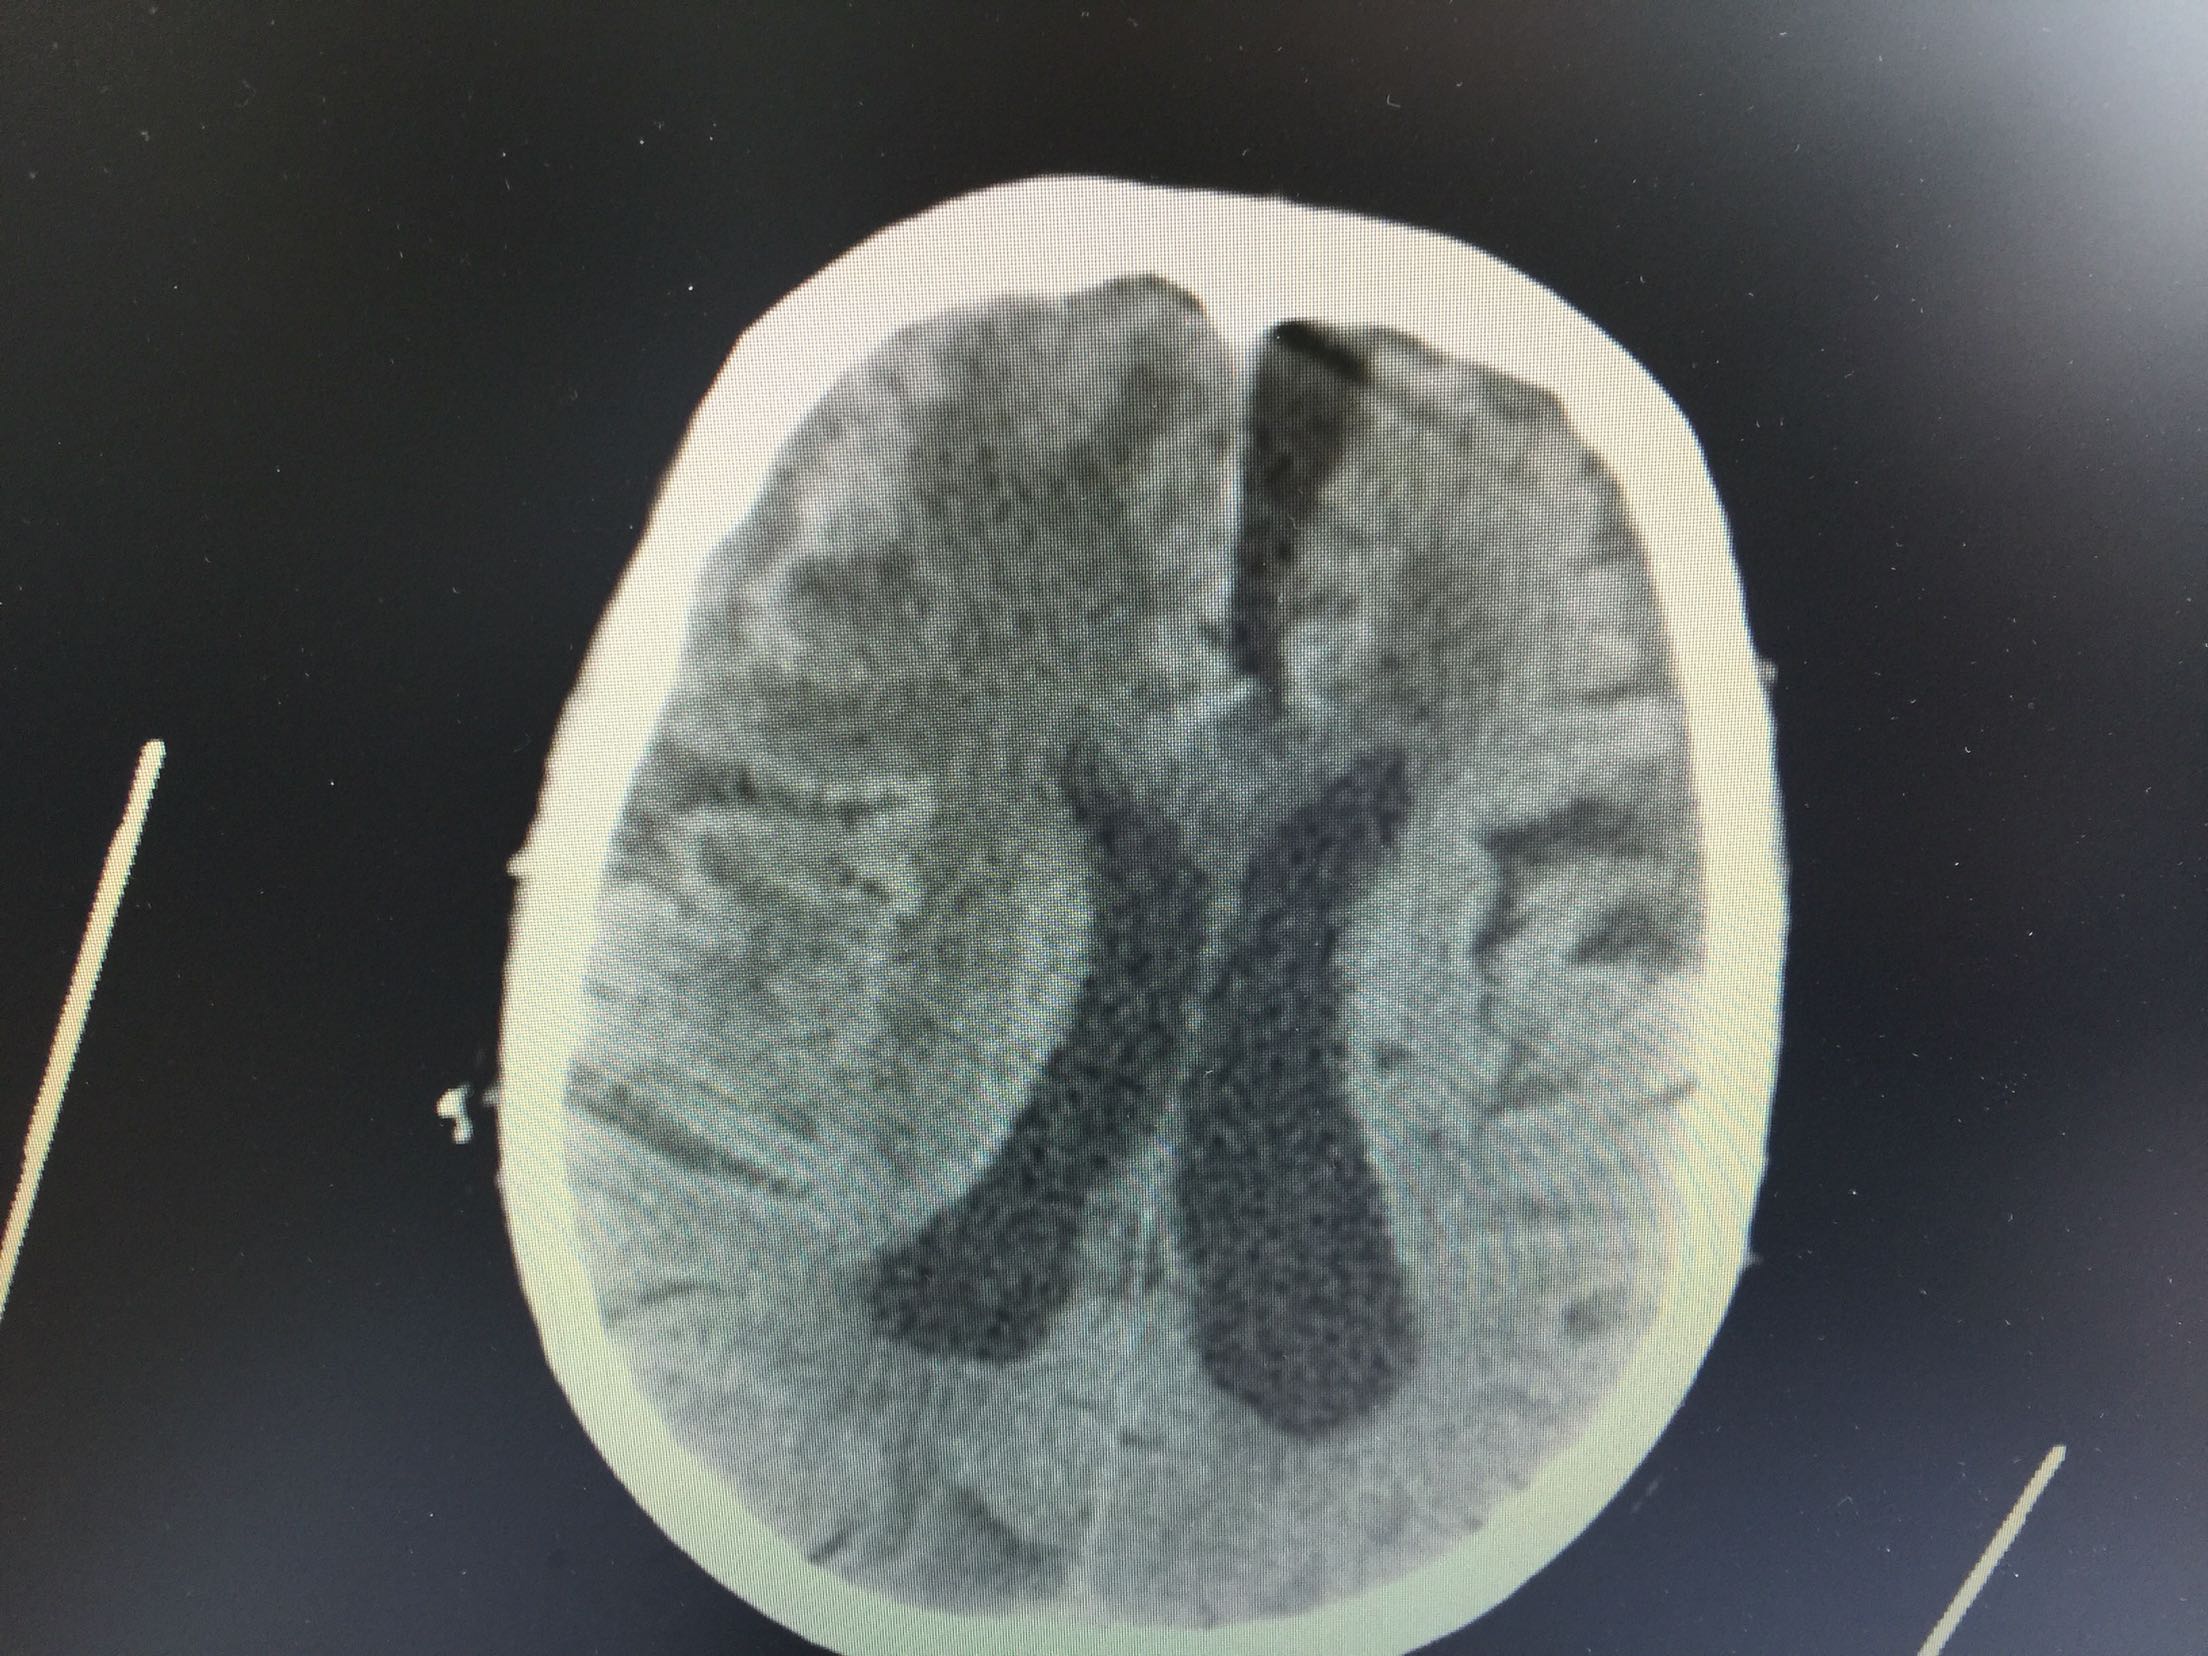

肺癌脑转移1例。

女,81岁,以“意识障碍1天”入院。

查体:浅昏迷,双眼向左侧凝视,双瞳孔等大正圆,直径3.0mm,对光反射灵敏,四肢不自主运动,肌张力正常,腱反射卄,Babinski征R-L-,脑膜刺激征阴性。

1.肺癌脑转移。 治疗:营养神经、脱水、抗感染、化痰、维持离子平衡治疗。

于4月20号临床死亡。